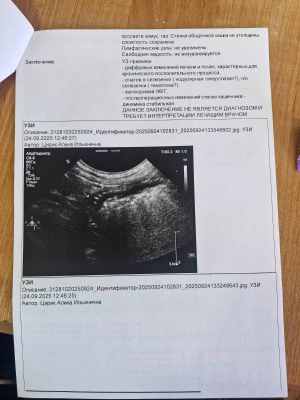

Колобушу сегодня возили в клинику. Новости не радостные. В лёгких на рентгене всё чисто. Но на УЗИ обнаружили два новых новообразования в селезёнке, пока они небольшие, нужно наблюдать. По мнению Шимширта, это скорее всего появились метастазы. Самое плохое, что так быстро появились. Сказал, следует наблюдать. Контрольный приём через месяц.